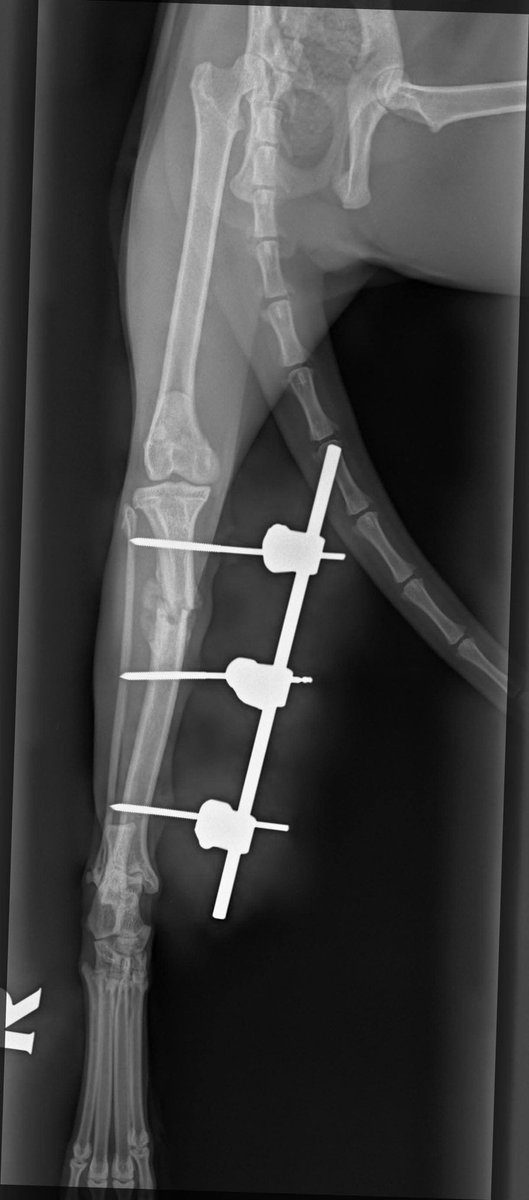

He is in intensive care and being looked after by our critical care team.